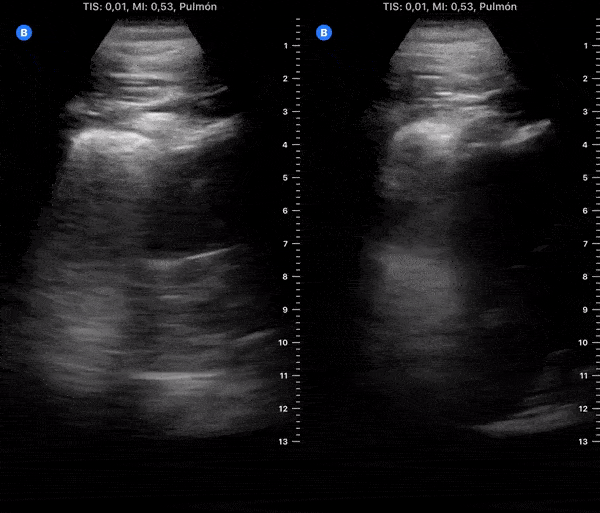

COVID 19 Lung US Disease Progression - Day 11

Day 11 after #COVID diagnosis. Less tired & cough, unable to endure small efforts. No dyspnea or red flag symptoms. No fever. SpO2 98%. #POCUS update: Bilateral subpleural consolidations, thick pleura & focal B-lines. @yaletung